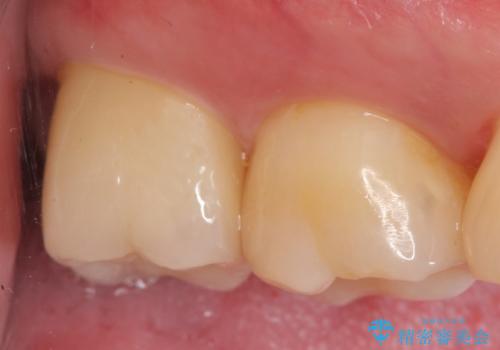

- 右上7の虫歯が大きく、他院にて抜歯と言われたが、なんとか残せないかと当院にいらっしゃった方の症例です。

自発痛の既往および持続痛を認めたため、カリエス除去後根管治療を行いました。

その後オールセラミッククラウンによる補綴を行いました。